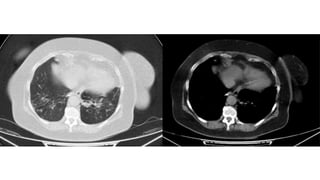

Punto máximo (9-13) Consolidaciones / Neumonía

organizada

●Consolidaciones

Etapa (días) TCTX Temprana (0-4) Normal / Vidrio esmerilado Progresiva (5-8) Aumento de vidrio esmerilado / Patrón “Crazy paving” Punto máximo (9-13) Consolidaciones / Neumonía organizada Absorción (> o = a 14) Bandas fibrosas / Vidrio esmerilado